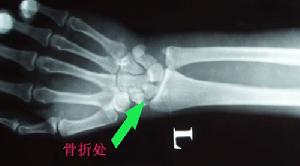

3、X線檢查

除正、側位X線攝片外,尚應根據傷情拍攝特殊體位相,如開口位(上頸椎損傷)、動力性側位(頸椎)、軸位(舟狀骨、跟骨等)和切線位(髕骨)等。複雜的骨盆骨折或疑有椎管內骨折者,尚應酌情行體層片或CT檢查。

腕舟狀骨骨折X線平片的診斷意義 常規腕關節正側位片、舟狀骨位片可以清晰顯示關節間隙,腕骨夾角以及其他腕骨結構,對診斷腕舟狀骨結節骨折,尺橈骨遠端骨折及其他腕骨骨折脫位很有意義。但常因投照技術、體位、角度等因素使舟狀骨骨折漏診。同時還有一部分穩定型骨折,因骨折端嵌插,其平片常呈高密度影,未見低密度骨折線而漏診。本組3例複習初次X線平片為高密度影,當時未行固定,致骨折線明顯後才確診。有學者認為,傷後2~3周,隨著骨折斷端骨質壞死及血腫的吸收,骨折處間距加大,可以提高X線平片的診斷率。但亦有學者研究則認為傷後2~3周與初次的X線表現常無變化。本組2~3周X線確診率為37.5%,4~6周為100%。